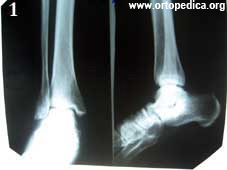

1. Рентгенография стопы - артроз подтаранного сустава

Рентгенография стопы - артроз подтаранного сустава Спиральная компьютерная томография стопы - плосковальгусная деформация